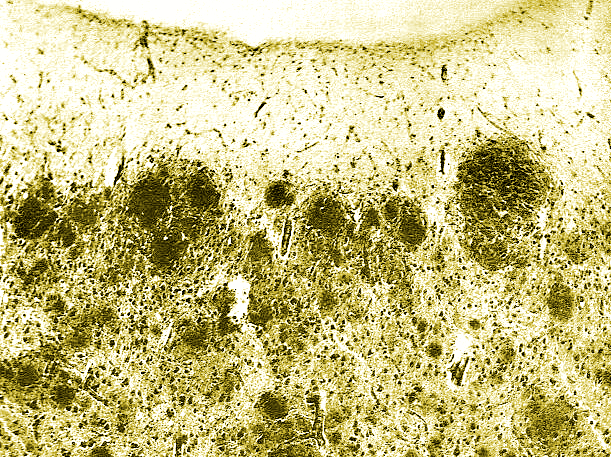

New acousmatic piece commissioned by Ina-GRM and Studio éOle. This is a 9 channels piece, octophonic system + solo speaker, based on the early works of Dr Aloïs Alzheimer on the neurological desease named after him. I used extracts of two Alzheimer’s publications (1906 and 1911) upon the two cases he studied and specifically the Auguste Deter case which led him on the track of this desease. Two comedians have recorded those texts, Pascale Calvet for the french translation of the Mme D. case and Ulrich Funke for the original german version of Johann F. case.